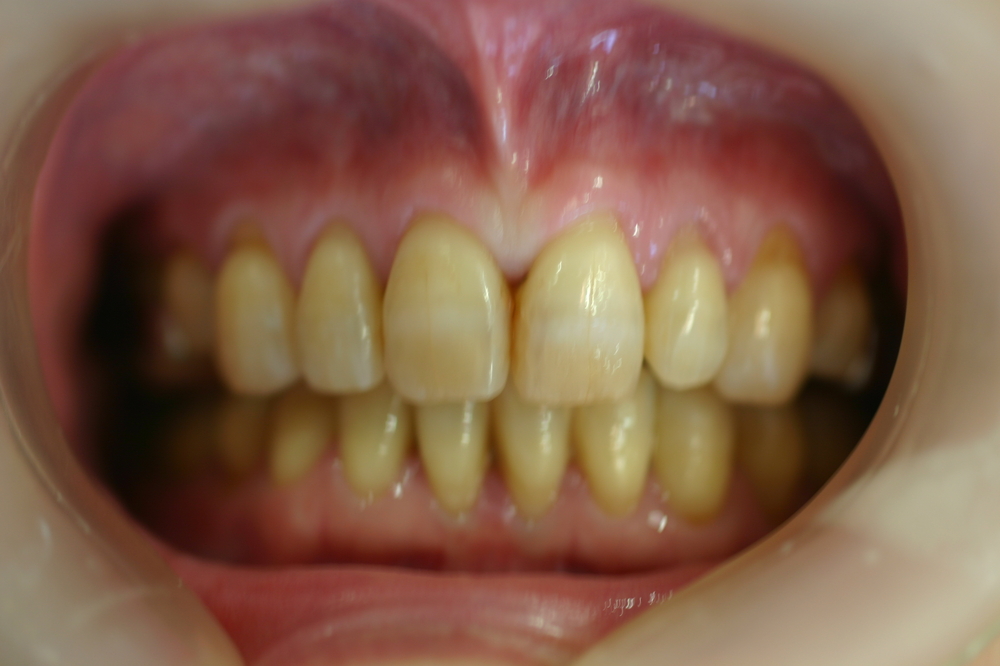

上顎の中央の歯一本が前にとびだしている治療例

Before

上顎の中央の歯一本が前にとびだしている症例です。これだけ前に出ていると、歯を抜いて並べていくか、何本かの歯を削らないときれいに並べられません。

このケースは、上の顎に矯正用のミニスクリュー{矯正用ミニインプラント}を入れて、歯を抜かず、削りもしないで、しかも上顎だけの矯正で治した症例です。

矯正用インプラントを使うことによって歯並び全体を後方に動かすことができるようになったため、このような治療ができるようになりました。

年齢 20代

治療期間 8ヶ月

治療費用 800,000円

治療のリスク 特になし